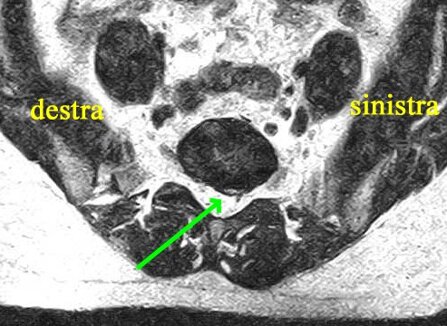

Non vi è generalmente proporzione tra l’entità del quadro radiologico (alterazioni rilevate alla tac e/o alla risonanza magnetica) e lo stato clinico e relativa sofferenza del paziente.

Può essere invece proposta la combinazione dell’ozono-terapia ecoguidata, con azione anti-infiammatoria e antidolorifica locale sulla patologia degenerativa (potenziata notevolmente dall’ecoguida, ossia dalla possibilità, mediante il contemporaneo utilizzo di un ecografo, di indirizzare con precisione l’ozono alle vertebre e ai dischi degenerati) e della scrambler therapy, capace di sostituire lo stimolo nocicettivo con uno nuovo stimolo favorevole al cervello.